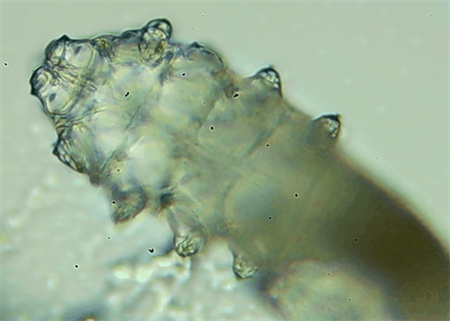

從一只眼睛的上眼瞼和下眼瞼處各拔3根睫毛,放在玻片上。

把玻片放到顯微鏡下觀察,通過電腦實時傳送的畫面,可以查看到這些拔下來的睫毛上是否有螨蟲。

結(jié)果,有6個人拔下來的睫毛上都發(fā)現(xiàn)了螨蟲。

這種螨蟲叫做蠕形螨,他們通常呈乳白色、半透明的細長狀,擁有四對腳。它們跟被子上的塵螨可不是同一種。